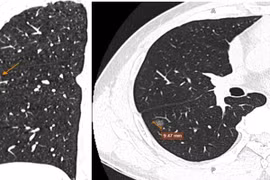

Đến viện kiểm tra vì đau tức ngực phải, người đàn ông được chẩn đoán mắc tăng sản dạng tuyến không điển hình (AAH) - tiền thân của ung thư biểu mô tuyến phổi.